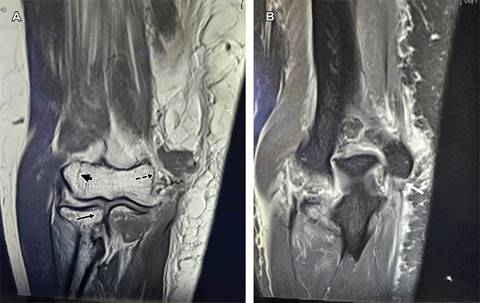

Figura 1: Imágenes de resonancia magnética de codo, se muestra en plano coronal en vista anterior (A) trazos de fracturas no desplazada del capitellum humeral (cabeza de flecha) y de porción medial de cabeza radial (flecha negra); desprendimiento del músculo braquial anterior (flecha punteada); en la vista posterior (B) lesión del ligamento colateral medial y de su fascículo posterior denominado ligamento de Bardinet (flecha blanca).